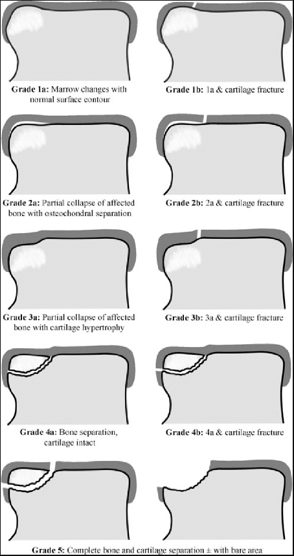

Hepple (1999) — МРТ-классификация

Модификация Berndt-Harty с учётом данных МРТ, введение подтипов для хронических повреждений:

| Стадия | МРТ-находки | Клиническое значение |

|---|---|---|

| 1 | Повреждение только суставного хряща; T2 — высокий сигнал в хряще, нормальная субхондральная кость | Часто бессимптомное; консервативное лечение |

| 2a | Повреждение хряща + перелом субхондральной кости + отёк костного мозга (T2-STIR — высокий сигнал) | Острое повреждение; иммобилизация |

| 2b | Повреждение хряща + перелом субхондральной кости БЕЗ отёка | Хроническое повреждение; хуже прогноз консервативного лечения |

| 3 | Отделённый, но не смещённый фрагмент (T2 — высокий сигнал по границе фрагмента = жидкость) | Нестабильный; показана операция |

| 4 | Смещённый фрагмент | Абсолютное показание к операции |

| 5 | Субхондральная киста (T1 — низкий сигнал, T2 — высокий) | Хроническое повреждение; требует костной пластики |

Hepple показал, что МРТ выявляет 30-43% ОХП, невидимых на стандартных рентгенограммах, и обосновал необходимость МРТ при клиническом подозрении.

Рис. 3. МРТ-классификация остеохондральных повреждений по Hepple (1999)